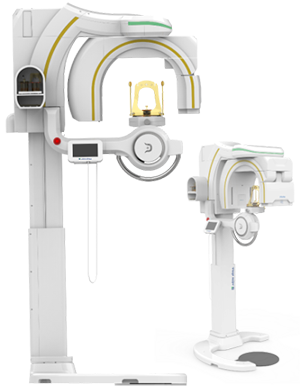

Cephalometric X-ray (optional)

Optional cephalometric arm, excellent for orthodontic practice